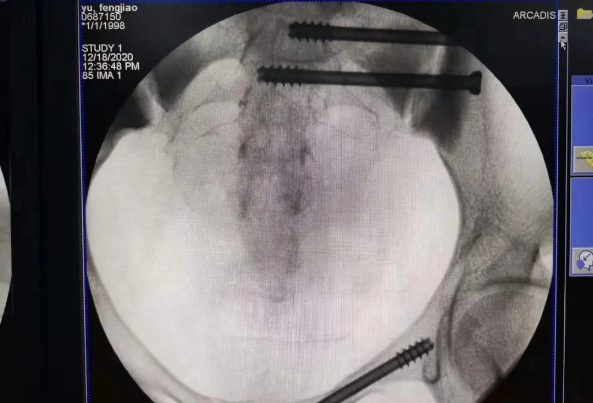

在南昌市第一醫(yī)院廖琦教授帶領(lǐng)下,由創(chuàng)傷骨科團(tuán)隊(duì)借助天璣?骨科手術(shù)機(jī)器人為患者“量身定做”最理想、最安全的教科書般的通道,完美安全微創(chuàng)完成手術(shù),并且手術(shù)時(shí)間明顯縮短,真正做到“指哪兒打哪兒”!更讓患者放心的是,天璣?骨科手術(shù)機(jī)器人的“穩(wěn)定手”機(jī)械臂進(jìn)行精準(zhǔn)定位,不用反復(fù)探尋。

由于天璣?骨科手術(shù)機(jī)器人的精準(zhǔn)及高效,可以使手術(shù)時(shí)間明顯縮短,因此在骨盆骨折手術(shù)后,在廖琦教授指導(dǎo)下,脊柱外科團(tuán)隊(duì)利用天璣?骨科手術(shù)機(jī)器人同樣為20歲女性腰椎骨折患者“量身定做”最理想、最安全的教科書般的通道,完美安全微創(chuàng)完成手術(shù),手術(shù)不僅時(shí)間縮短,并且出血和透視減少。